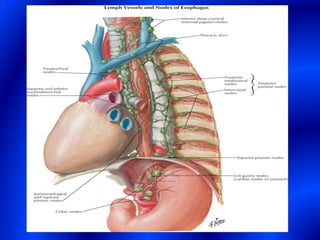

This document provides information about a barium swallow procedure. It begins with an introduction and overview of the embryology and anatomy of the pharynx and esophagus. It then describes the procedure itself, including preparation, technique, views obtained, and indications. Specific conditions that may be examined include pharyngeal and esophageal webs, foreign body impaction, scleroderma, dysphagia, mediastinal masses, and carcinoma. Diagrams are provided to illustrate normal anatomy and various pathological findings.